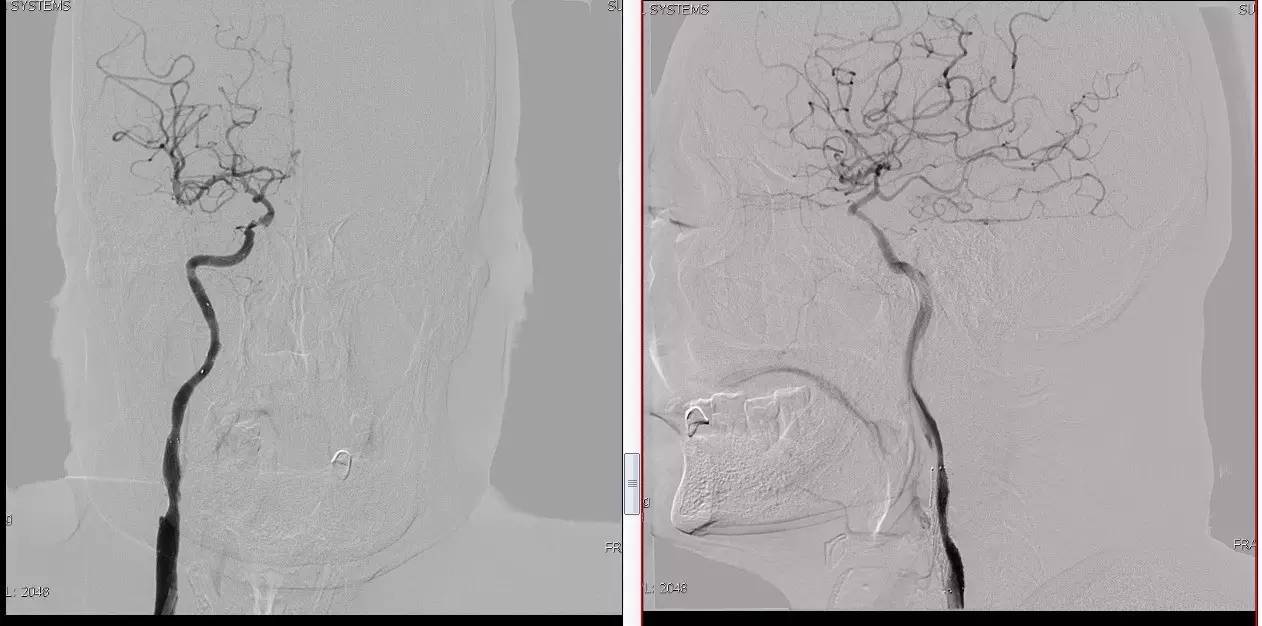

》当成颈动脉闭塞开通做,同时8F鞘内套以4F鞘给予微导管足够支撑力。

》避免后扩,分次治疗。

》术中脑保护,首选SPIDER。

★脑保护技术:病死率及卒中率从7.9%~9.1%降至1.7%,已作为CAS治疗常规。

远端滤网保护装置

滤膜网孔Φ为80~130 m,主要优点是不阻断血流,适合于绝大多数患者,能够在手术中随时造影监测操作步骤。

Spider FX™特点

导丝先行技术,目前通过性最好的远端栓塞保护装置。

术者可以选择“最顺手”、“最合适”的导丝辅助SpiderFX™通过病变。